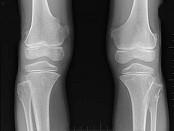

女,15岁,大腿远端可摸到肿块,无明显疼痛,请结合研提供图像,选择最佳答案()A.骨质增生B.软骨瘤C.骨肉瘤D.骨瘤E.骨软骨瘤

问题 女,15岁,大腿远端可摸到肿块,无明显疼痛,请结合研提供图像,选择最佳答案()

选项 A.骨质增生 B.软骨瘤 C.骨肉瘤 D.骨瘤 E.骨软骨瘤

答案 E